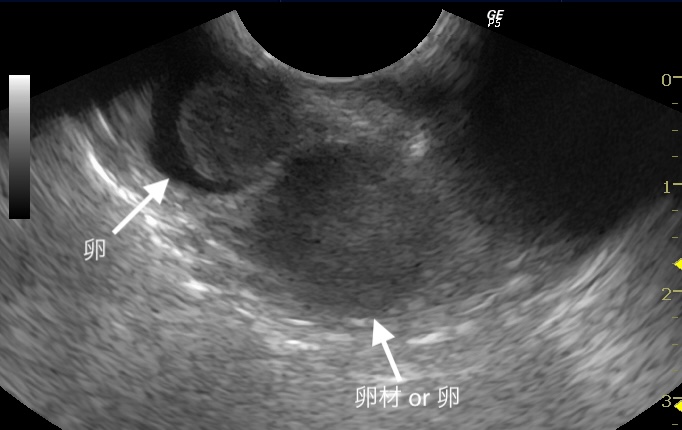

超音波検査では、卵管内に卵材か軟卵を疑う所見と、腹部下方の卵の周りには血流が確認できなかったため、卵墜症の可能性も考えました。